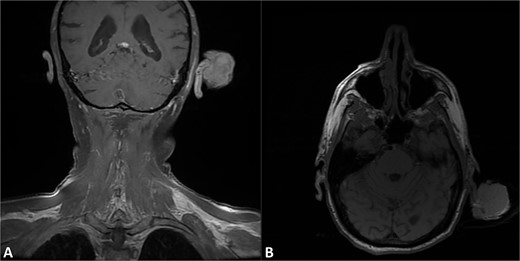

A 71-year-old unhoused gentleman presented to the emergency department for an enlarging 5.5 cm left helical mass (Fig. 1). Physical examination was otherwise unremarkable without cervical lymphadenopathy; House-Brackmann score demonstrated fully functional facial movement and the patient was without audiologic loss. Fat-suppressed, contrast-enhanced magnetic resonance imaging (MRI) of the head demonstrated a 5.5 × 2.2 × 3.6 cm polypoid mass extending from left anterior helix (Fig. 2A and B). A biopsy was compatible with PDS (Fig. 3A–D). Following multidisciplinary tumor board consensus, the patient elected to proceed with definitive surgical management and underwent left partial auriculectomy with bilateral advancement flap closure (Fig. 4A–C). The operating surgeon elected to obtain wider surgical margins to decrease the potential need for adjuvant therapy pending final histopathologic results given the concern for adequate surveillance. Specimen-driven intraoperative frozen pathologic analysis of the auricular skin and cartilage margins were negative for malignancy. Final pathology demonstrated atypical, spindled cells involving the underlying cartilage which stained negatively for keratins (AE1/AE3, CAM5.2), p40, S100, CD21, and CD35. These features, along with additional negative stains performed on the biopsy including p63, SOX10, desmin, and ERG, supported a diagnosis of PDS (Fig. 3E and F). No other adverse tumor features including LVI or PNI were identified; surgical margins were widely negative with the closest tumor margin identified at 1.5 cm. Final pathologic stage was pT3cN0M0 (staged according to AJCC 8th edition for head and neck sarcoma). Given the tumor size, tumor board recommended consideration of adjuvant radiation therapy (RT); however, the patient was subsequently lost to follow-up and failed to present to his 3-week postoperative visit given his challenging socioeconomic status and unhoused status.

T1 fat-suppressed post-contrast MRI of the head in the A) coronal and B) axial sections demonstrating pedunculated mass of the left helix with preservation of the underlying cartilaginous structures.